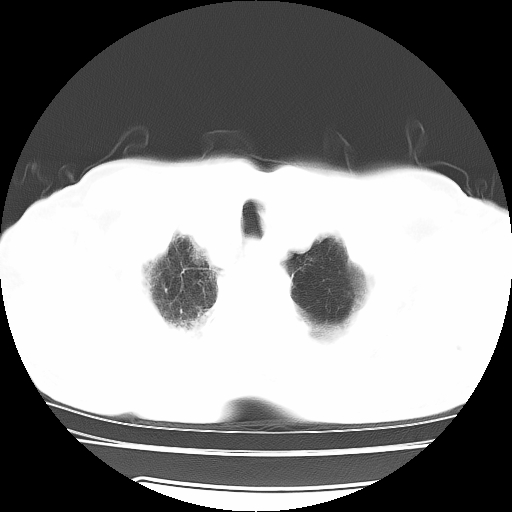

男,71岁,咳嗽,气喘10年,再发并咯血.胸片见气胸

考虑  左肺中心型肺癌伴阻塞性肺炎,肺不张,纵膈淋巴结肿大。慢支炎,肺气肿,左侧气胸肺压缩5%

左侧中央型肺癌伴纵膈淋巴结转移。

左肺中心型肺癌伴阻塞性肺炎,肺不张,纵膈淋巴结肿大

1)考虑左肺中心型肺癌伴阻塞性肺炎、左肺下叶肺不张、左侧肺气肿,纵膈淋巴结转移。2)左侧气胸(肺组织压缩约5%)。

左肺中心型肺癌伴阻塞性肺不张、肺气肿 。

1)考虑左肺中心型肺癌伴阻塞性肺炎、左肺下叶肺不张、左侧肺气肿,纵膈淋巴结转移。2)左侧气胸。